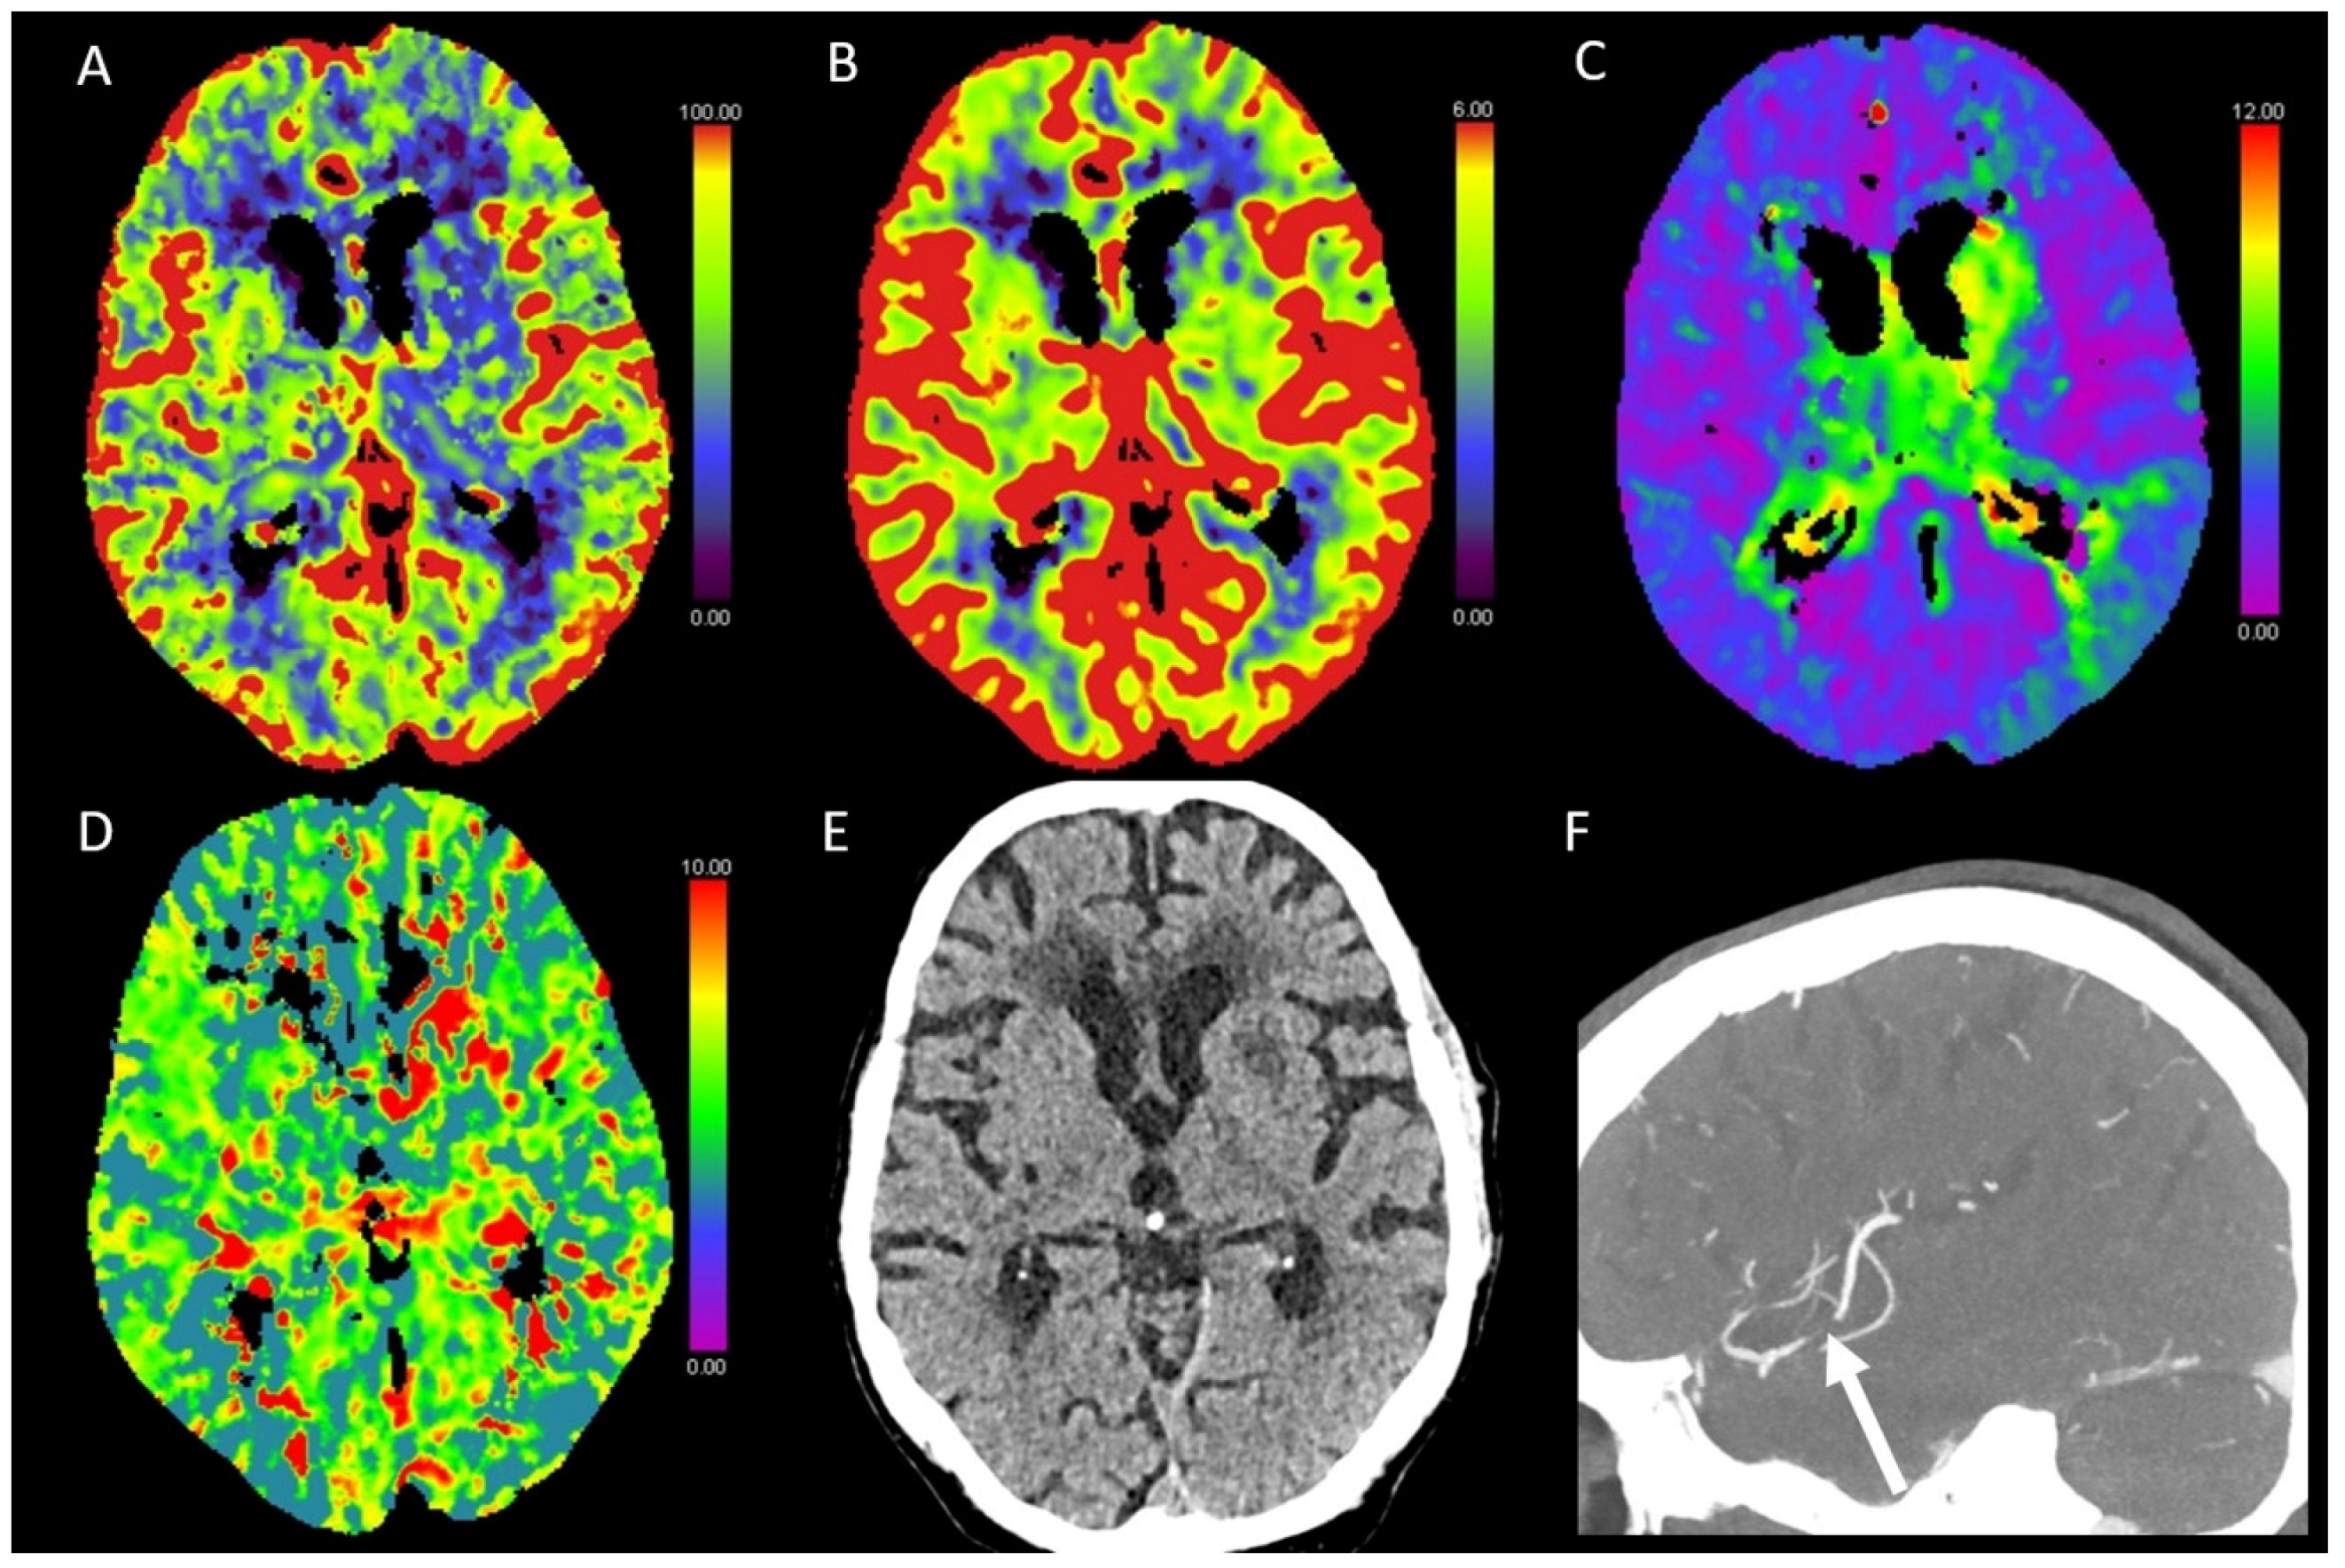

3.6. Vasospasm